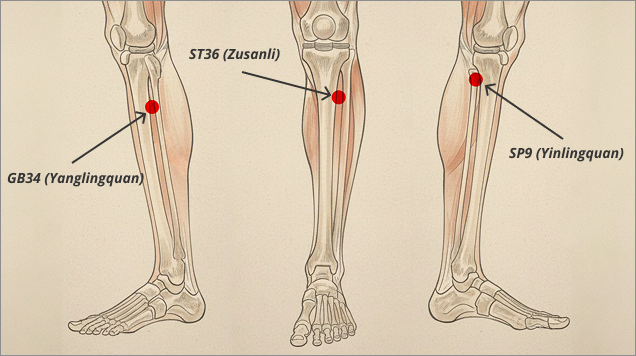

Magnesy o odpowiednio dobranym polu magnetycznym zostały

rozmieszczone dokładnie tam, gdzie znajdują się strategiczne

punkty akupresurowe stawu kolanowego, w tym punkty

ST36 (Zusanli), SP9 (Yinlingquan) czy

GB34 (Yanglingquan). Punkty te już w Tradycyjnej

Medycynie Chińskiej znane były ze swojego wpływu na układ

kostno-stawowy.

stymulacja punktów akupresurowych ST36, SP9 i GB34

stymulacja punktów akupresurowych ST36, SP9 i GB34